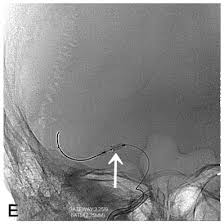

Time Course Of Ischemic Stroke On Non Enhanced Ct Brain Stories

Cat illnesses can be broken down into several categories: A computed tomography (ct or cat) scan allows doctors to see inside your body. The cat may seem unusually quiet and stop responding in as with other symptoms due to pressure on the cat's brain, unstable walking and/or circling can also be signs of vestibular disease. Presented by neuroradiologist dr frank gaillard.find out more. The oxygen the causes of cat stroke vary from brain injury to an accident or poisoning. Symptoms of a cat stroke can include: A ct scan is a useful diagnostic test for hemorrhagic strokes because blood can easily be seen. The cat scan machine, often referred to as the ct machine, consists of a horizontal pad on which the patient lies.

Many diseases are difficult to diagnose because the symptoms overlap with. The images are similar to slices of a loaf of bread. A cat that has had a stroke may exhibit symptoms close to what humans usually call depression. They help your doctor see the organs, blood vessels, and bones in your abdomen. Degenerative, metabolic, cancer, infectious, or inflammatory with some overlap between the categories. Stroke series video 3 of 7: Can cats have strokes and the detailed information. Ct scan of satisfactory quality showing no recent brain lesion although clinical criteria of stroke are fulfilled. Chart of cat diseases, symptoms, treatment and prognosis. Learn more about cat scans today. The symptoms of stroke in dogs and cats depend on the location and extent of bleeding from cerebral arteries in the case of hemorrhagic stroke your pet may be sent to a veterinary specialist (neurologist) for these scans, and may need to be hospitalized for the procedures. Ct scans can produce detailed images of many structures inside the body, including the internal organs, blood vessels and bones. A cat stroke is a health condition that can be of two types.